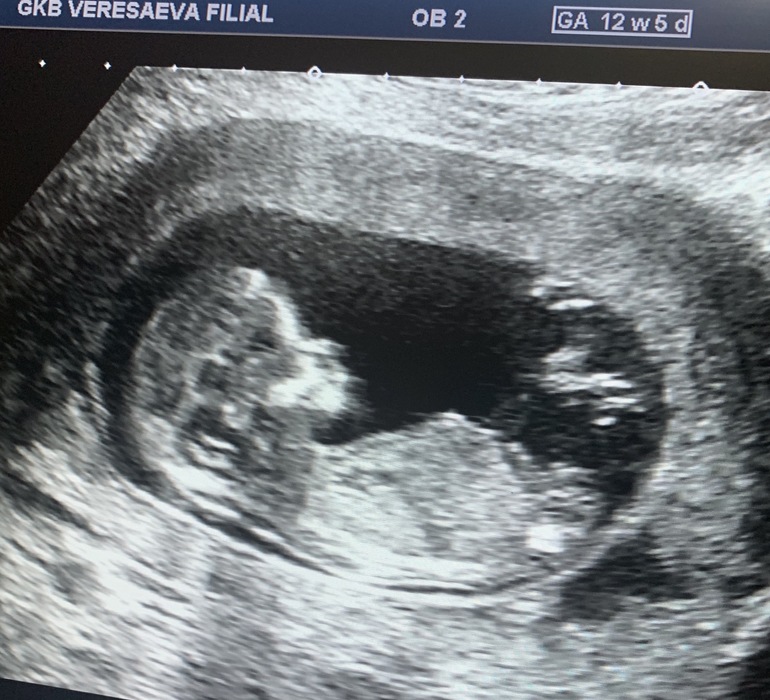

На девочку похожа по бугорку. Нам в 12 нед уже точно сказали, и каждое узи врачи говорят, что это точно мальчик. Вот фото мальчика нашего в 12 нед, у Вас совсем по-другому

Девчушечка , половой бугорок не торчит , а лежит ровно )

У вас немногт не так. Тут девочка скорее

ну так они и угадывают с попадением 50/50 на таком сроке. Мне в 12 недель с 99% уверенностью сказали девока и даже показали типо вот смотри. А в 18 недель эта 99% девочка превратилась в 100% мальчика )))

Sunflower, ну, у меня показало мальчика прошлый раз, а родилась девочка, а в этот раз показывает девочку😂🤣

Гадаем пол по фото)) Сегодня у нас праздник!